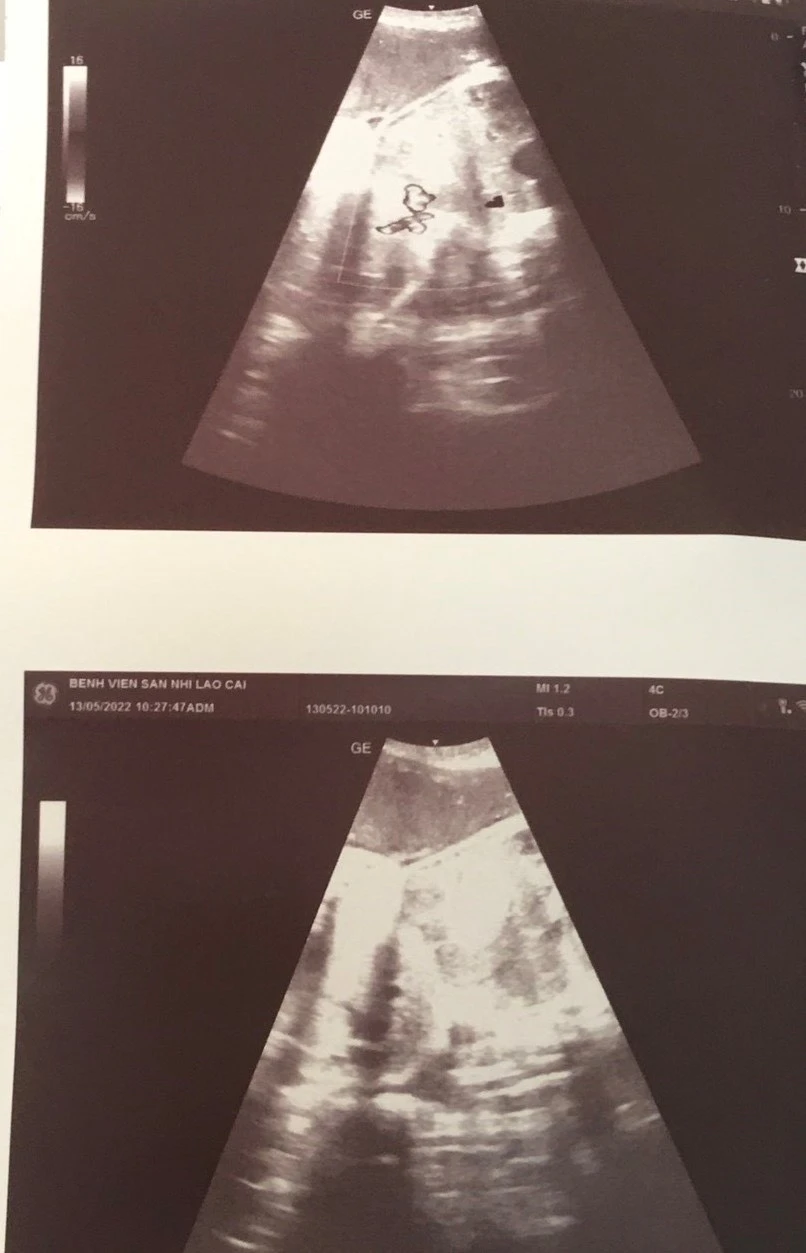

Kết quả siêu âm chẩn đoán hình ảnh cho thấy hai bé dính nhau ở phần bụng, một bé sứt môi, hở hàm ếch. Đây là trường hợp song thai cùng trứng, có cùng bánh nhau và chung dây rốn.

| Hình ảnh siêu âm của thai của sản phụ. |